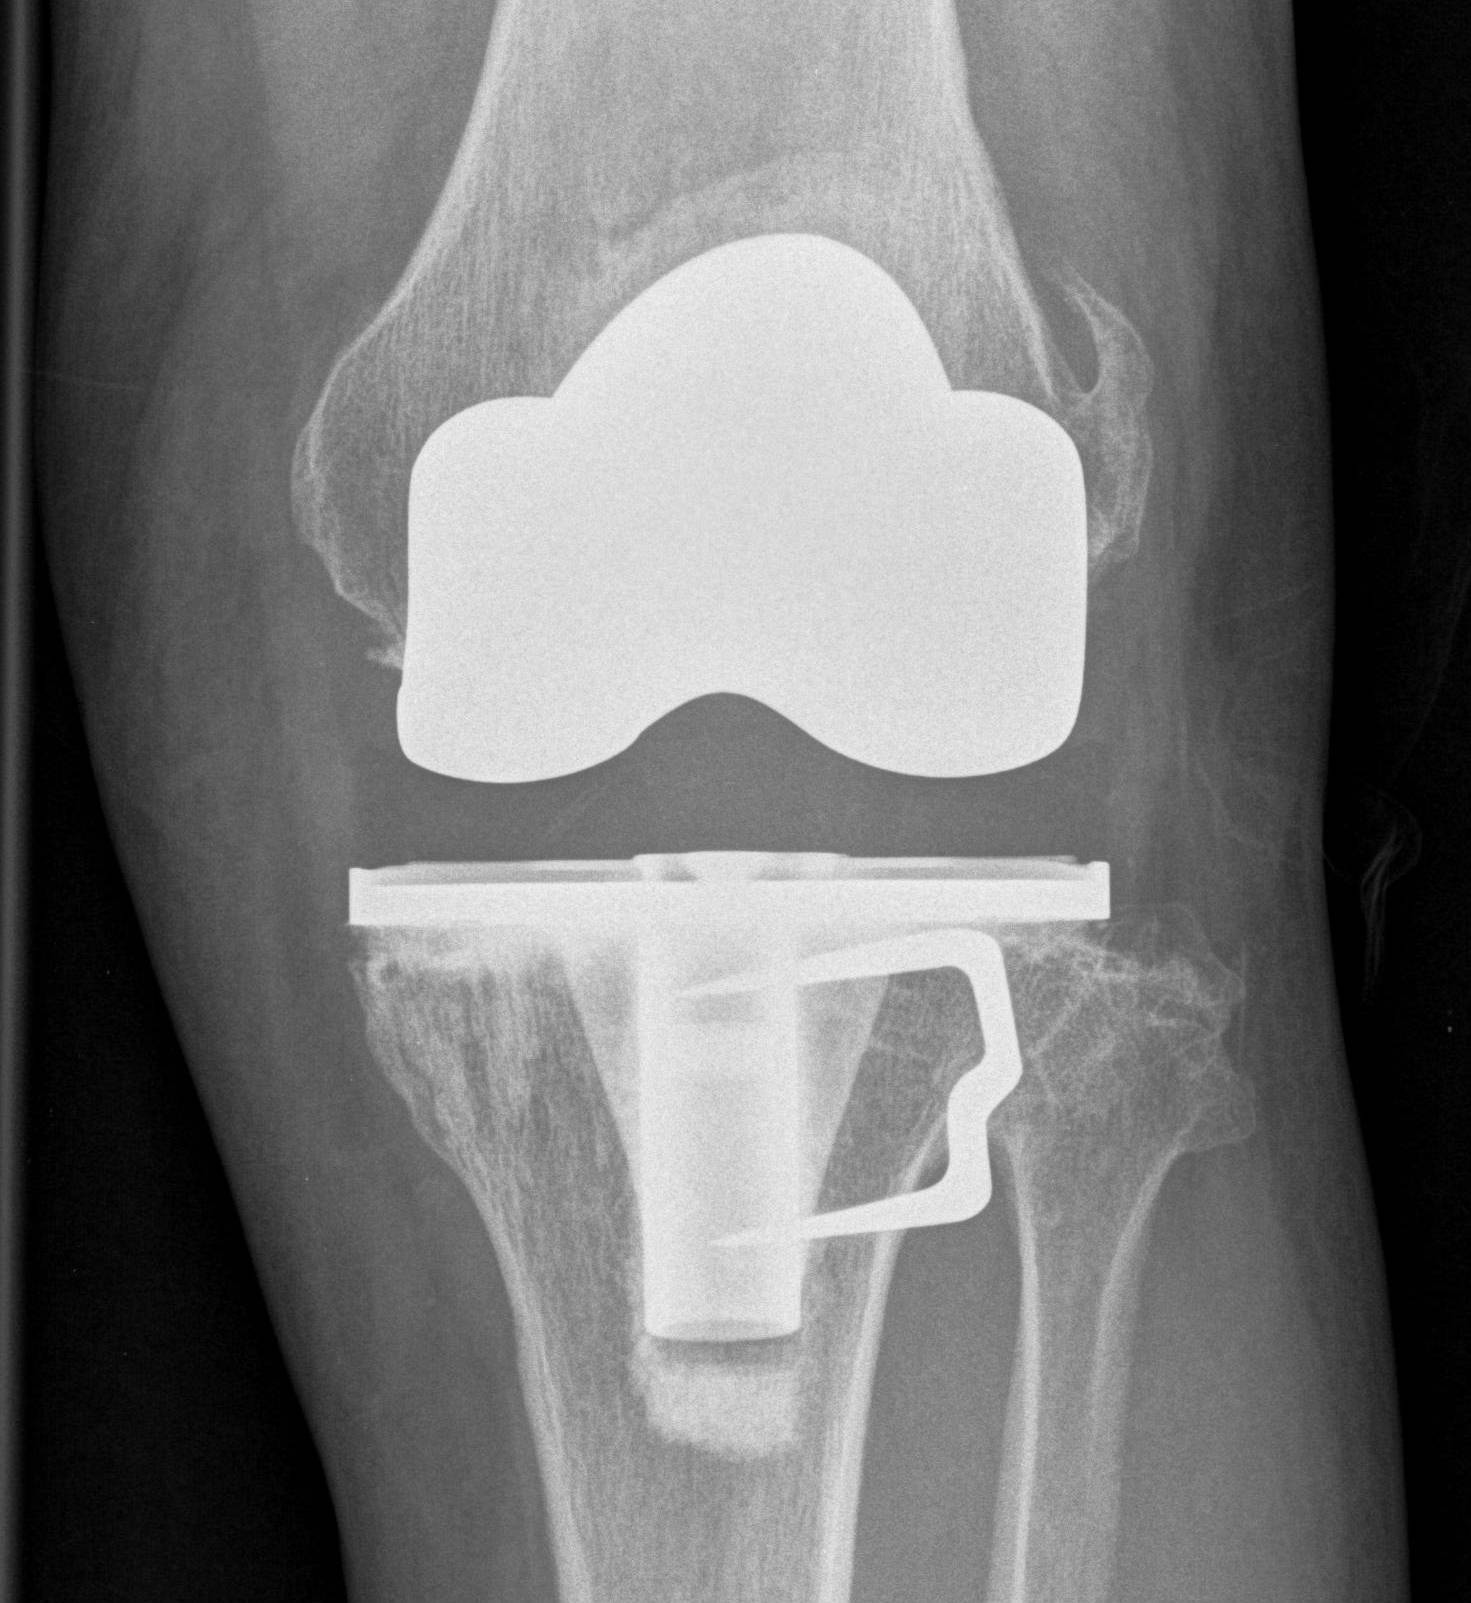

3. Offset tibial shaft medially

Seen with closing wedge

- need offset stem to avoid lateral overhang

- more common when large corrections have occurred

- have revision stems available